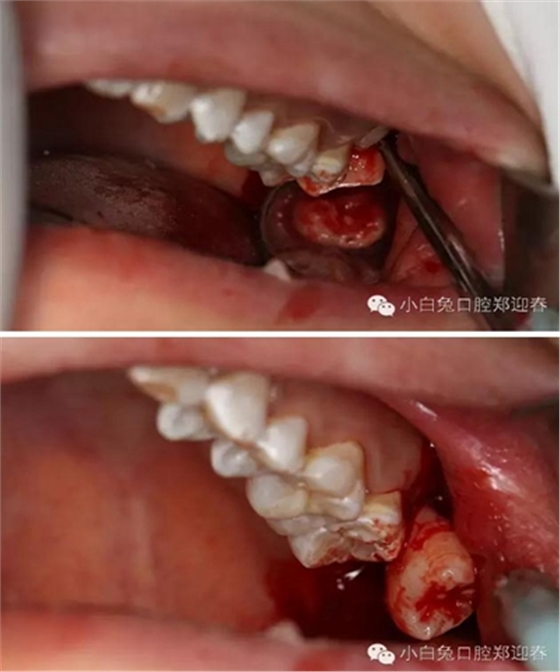

渦輪動(dòng)力切割阻力牙冠

“T”型分割近中阻力冠

分別去除近中阻力冠的頰和舌部的牙冠

順著牙長(zhǎng)軸的方向挺出牙根,這樣可以避免因?yàn)檠栏D(zhuǎn)對(duì)神經(jīng)管的影響。